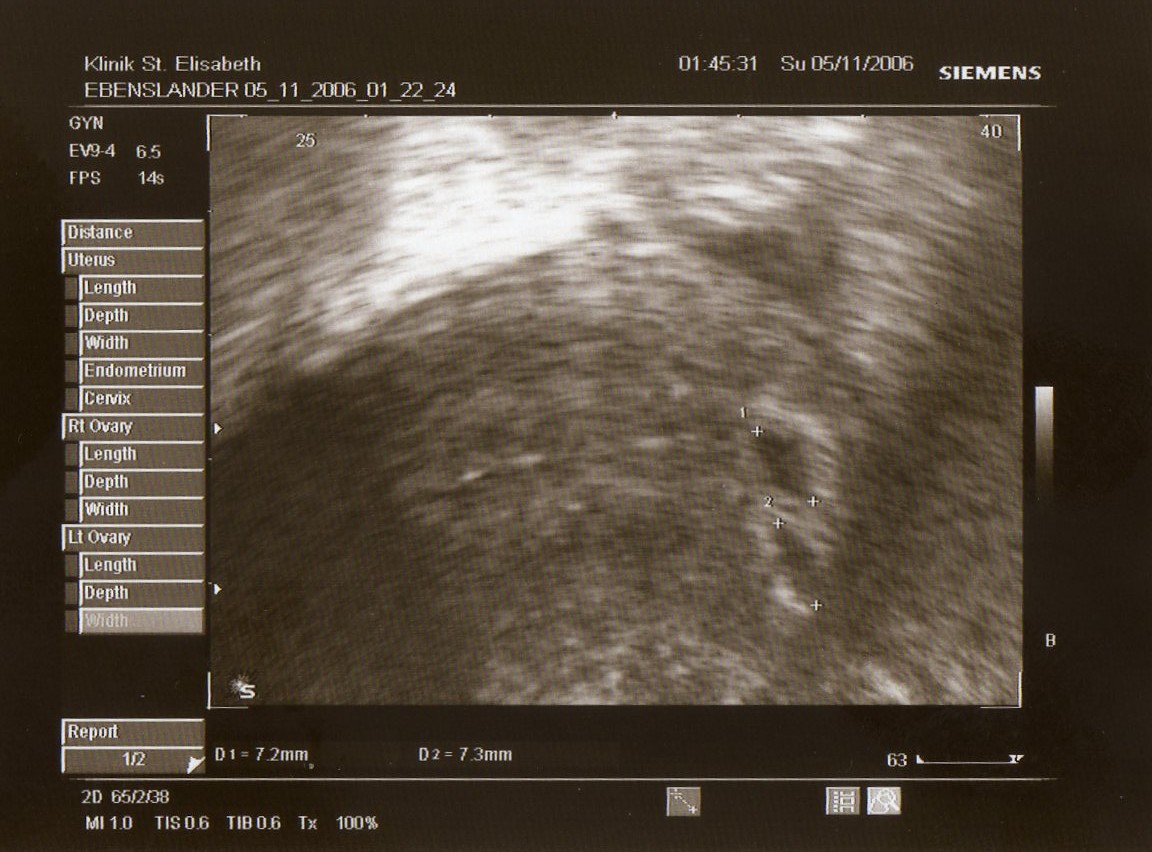

Und dann kam der US... tja ... es sind tatsächlich 2 kleine Furchthöhlen von jeweils ca. 7mm zu sehen !

Die Gebärmutterschleimhaut ist 4cm dick, an den Eierstöcken ist schön das Gelbkörperhormon ... also alles wie es sein soll ! JUHU

Hier anbei das Bild von den 2 Fruchtblasen ...